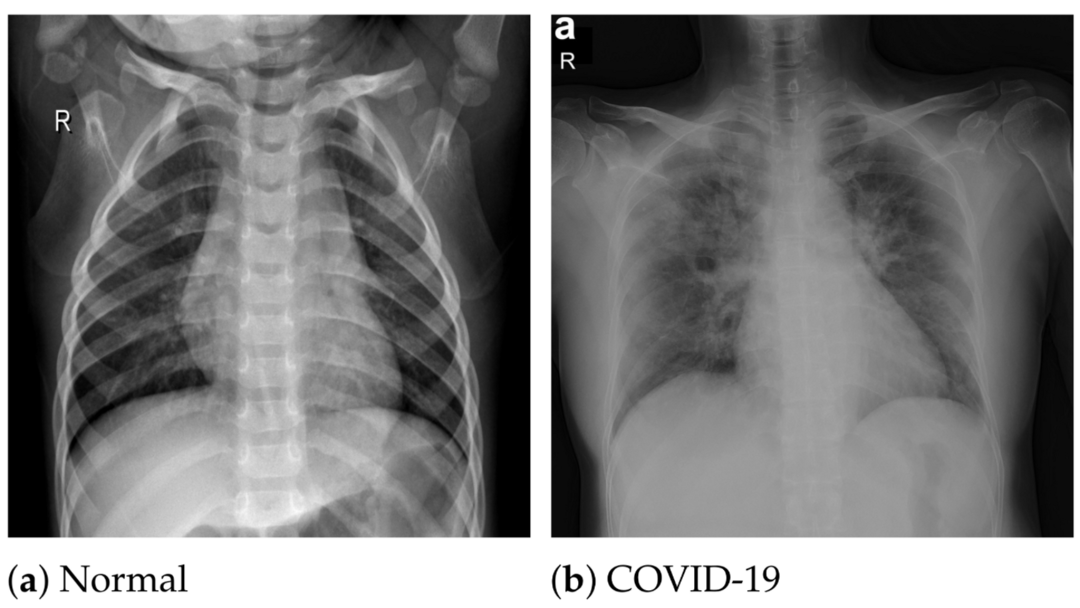

1月20日(周四),官方公布:苏格兰的专家们开发了突破性的人工智能AI技术,能够在短短几分钟内非常准确诊断出是否患有新冠,比PCR核酸检测要快得多。

西苏格兰大学UWS的这项研究使用X光技术,将扫描结果与大约3,000张图像包括新冠患者,病毒性肺炎以及健康群体的数据库进行比较。

西苏格兰大学UWS的这项研究使用X光技术,将扫描结果与大约3,000张图像包括新冠患者,病毒性肺炎以及健康群体的数据库进行比较。然后使用人工智能程序——用于分析视觉图像的算法,来进行诊断。

专家说,在检测过程中发现:这项技术检测病毒的准确率高达98%以上。

据悉,官方希望这项新技术能够缓解世界各国卫生系统的压力,特别是在那些PCR核酸检测能力十分有限的国家。

该项目的负责人,西苏格兰大学UWS情感和人类计算SMART研究中心主任Naeem Ramzan教授表示:长期以来,人们一直需要一种能够快速且准确检测新冠的可靠工具,而随着Omicron变种的上升,这一需求变得尤为明显。

“在感染新冠的早期阶段,新冠症状在X光片中是不可见的,因此必须注意,该技术不能完全取代PCR核酸检测。但是仍然可以准确诊断出大部分阳性患者,而且费时极短。”

西苏格兰大学UWS研究创新和参与副校长Milan教授补充说,这项新技术将是潜在改变全球新冠检查规则的技术。

据悉,目前该校研究人员正计划扩大对其X光检测技术的研究。他们将比对更多的X光片,以审视这项技术是否可以在医院和诊所广泛推广。